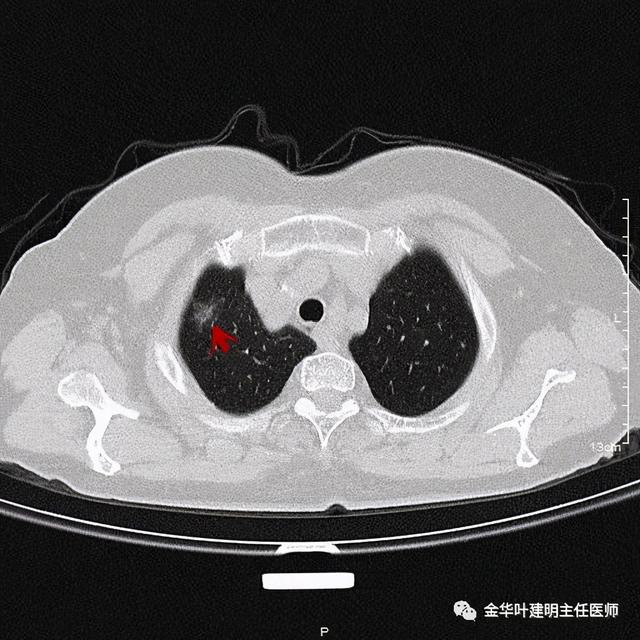

患者为女性 , 今年76岁 , 平时体质甚好 , 家务及地里劳动都胜任 , 头发仍乌黑(我自己倒有一半白发了) 。 肺功能与血气分析正常 。 CT检查图像如下:

可见右肺上叶混合磨玻璃结节 , 有明显分叶征 , 瘤肺边界虽然欠清楚 , 但轮廓比较清晰 。 看着也许会考虑炎性 , 但总觉得其比较僵硬 , 看去不舒服 。 这种病灶一是如果持续存在就极可能是肺癌 , 二是靶扫描显示更清晰的细节 , 如果瘤肺边界还是清楚的 , 也基本是肺癌 。 我们回顾发现其于2019年3月在我们医院做过CT平扫 , 当时报告如下: